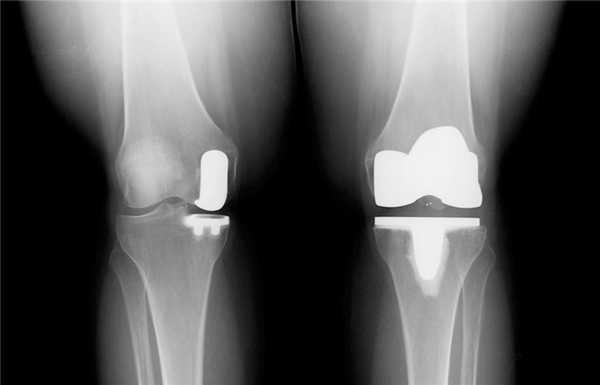

Если сустав поражен указанным на изображении образом, то возможна его частичная замена.

Основной метод лечения – постановка эндопротеза вместо поврежденного сустава. Раньше выполнялось преимущественно тотальное эндопротезирование коленного сустава, однако сейчас активно развивается другое направление – одномыщелковое (частичное) эндопротезирование.

Имплант на рентгене.

Как это выглядит после операции.

Одномыщелковая замена сустава на рентгене.

Две техники операции у одного пациента.

Один пациент, но две разные техники замены коленного сустава: справа — тотальная, слева — одномыщелковая.